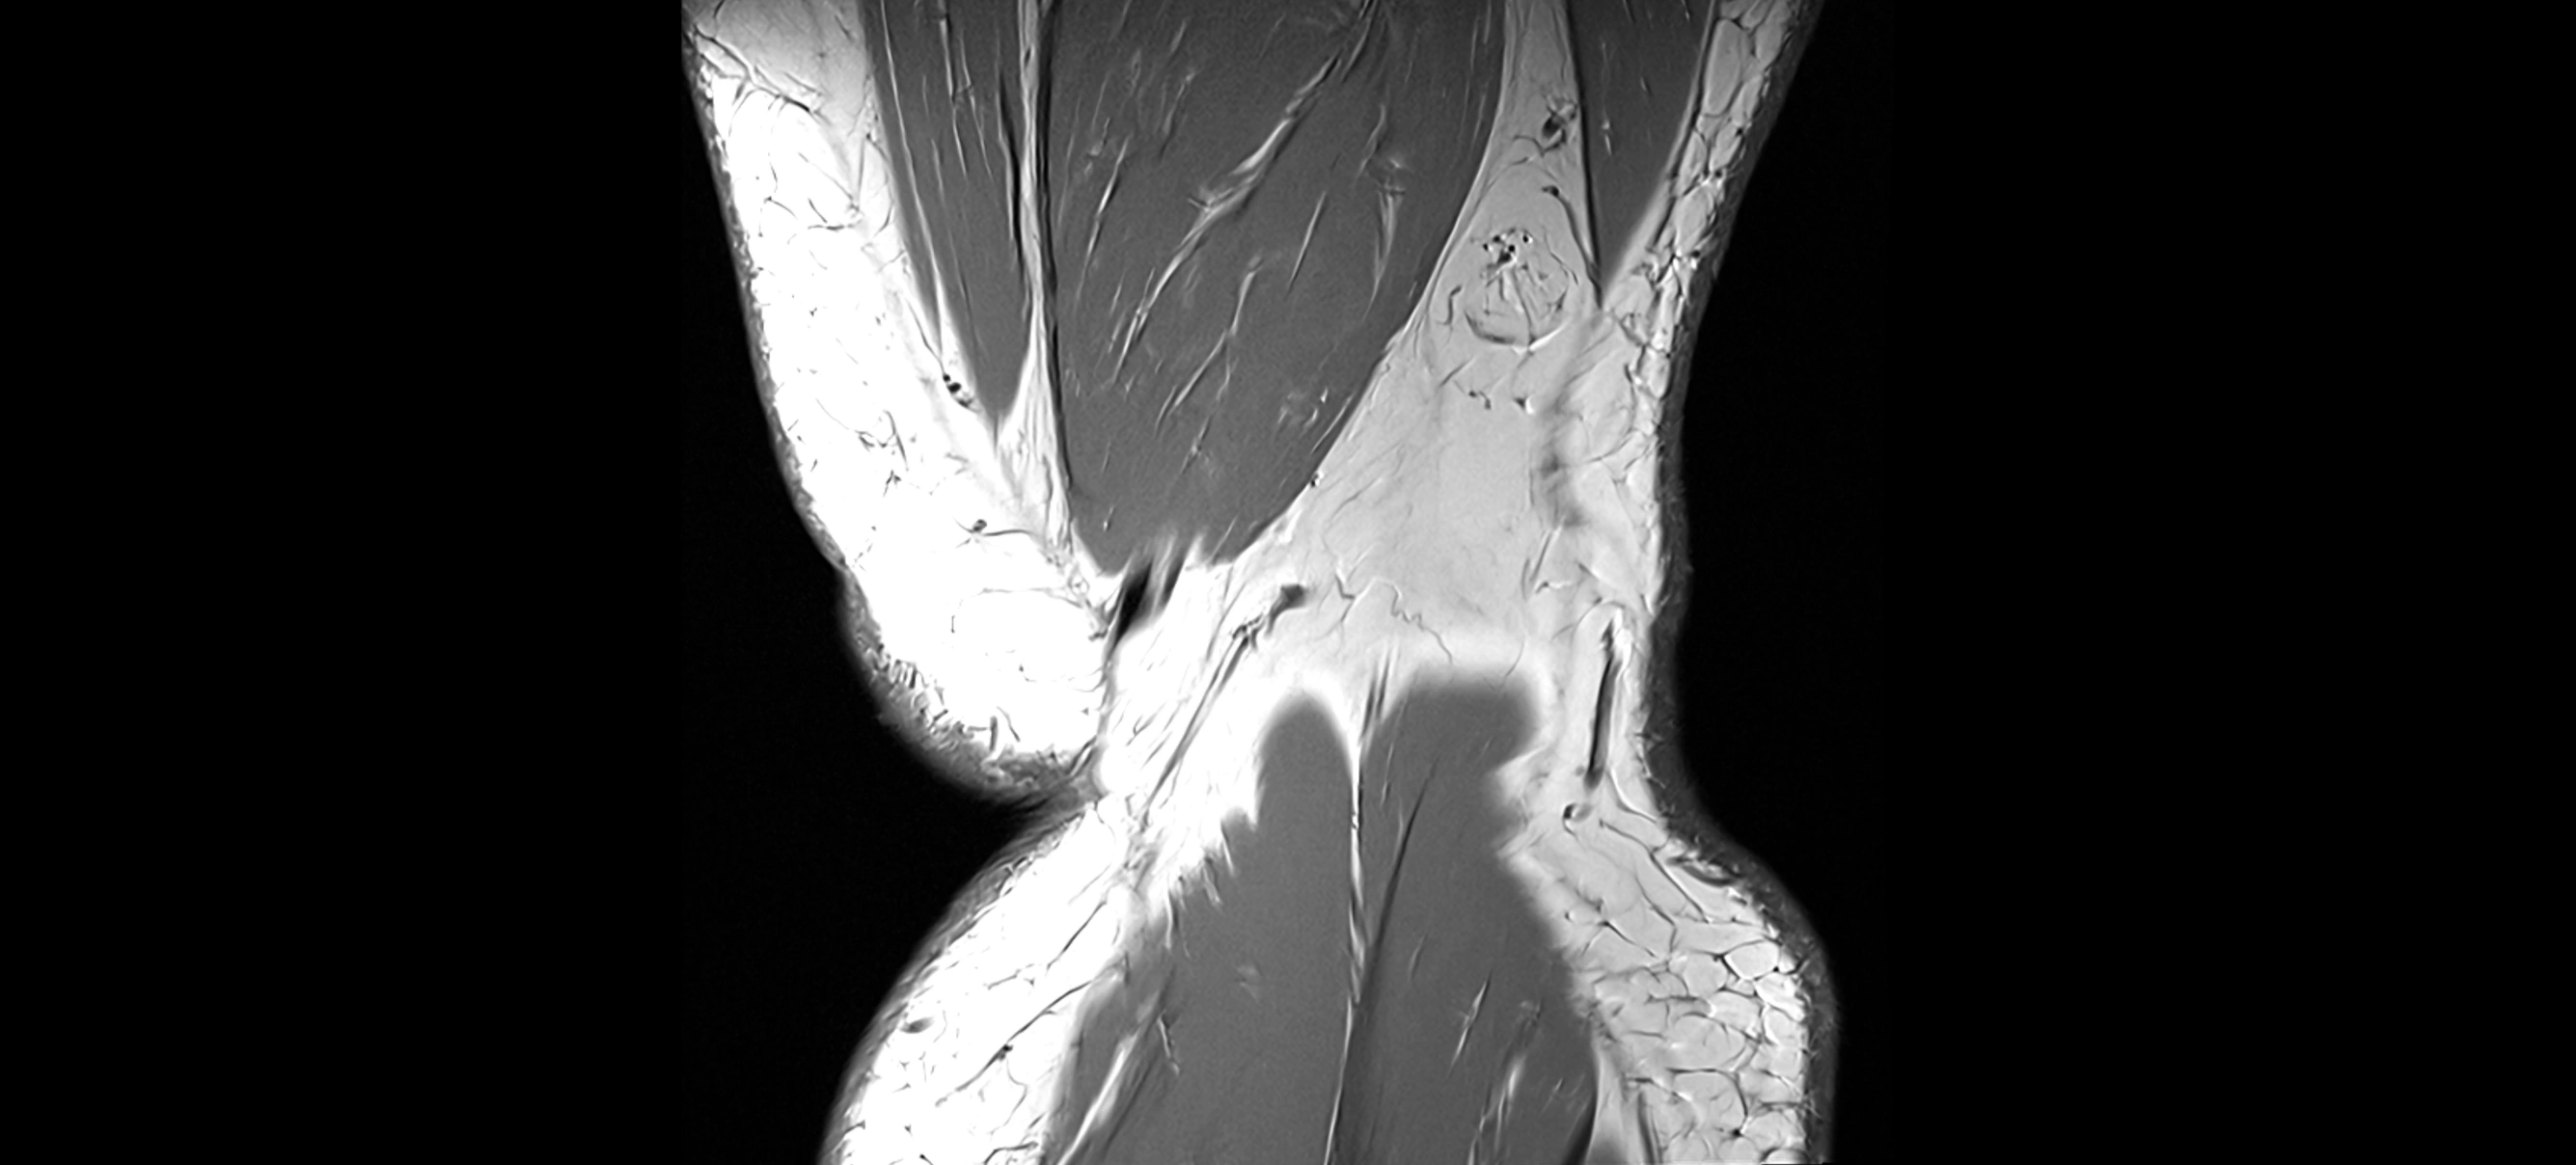

MRI images

image